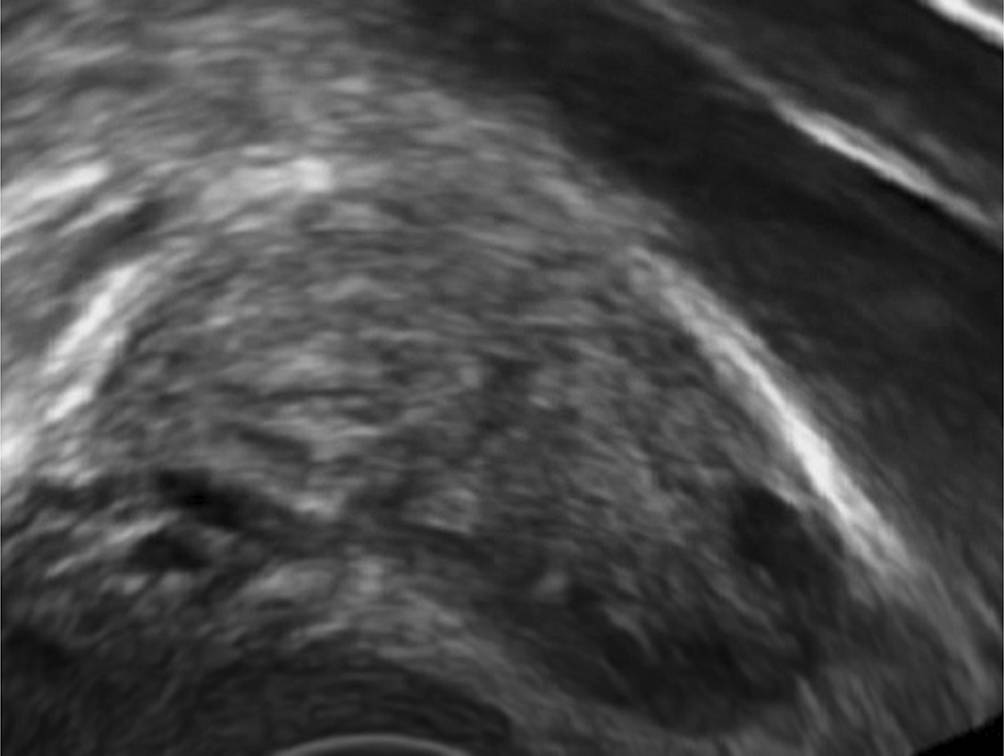

Beim „blob“ zeigt sich eine inhomogene, meist nicht an allen Seiten scharf abgegrenzte Struktur, die nicht dem Ovar und dem Uterus zugeordnet werden kann (58 % aller Fälle; Abb. 2). Schon etwas weiter ist eine Schwangerschaft, die sich als „bagel“ zeigt und wo im Zentrum der „blob“-Struktur ein leerer Fruchtsack gesehen werden kann (21 % aller Fälle; Abb. 3). Den Fruchtsack mit darin erkennbaren embryonalen Anteilen sah man in einer Metaanalyse in 13 % der Fälle, bei denen sich eine PUL als ektope Schwangerschaft herausgestellt hatte ([3]; Tab. 1).

Abb. 2

Das „blob sign“: Ein normales Ovar mit Follikel liegt der Iliakalvene an, in der Bildmitte beginnt eine unscharf abgegrenzte Struktur, die sich bei Palpation anders als das Ovar bewegt. Dieser „Klecks“/„blob“ ist die ektope Schwangerschaft